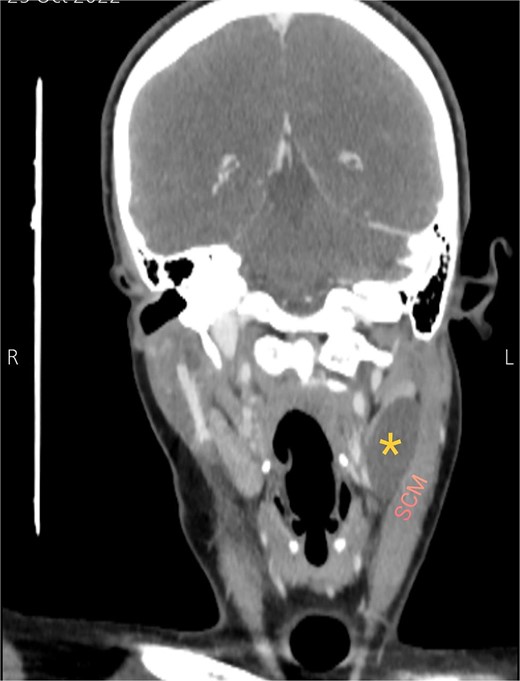

Soft tissue ultrasound revealed a well-demarcated, oval-shaped, homogeneously hypoechoic with internal debris mass and posterior acoustic enhancement, measuring about 3.8 × 4.7 cm. Axial (Fig. 2), sagittal (Fig. 3), and coronal (Fig. 4) neck computed tomography (CT) scans with intravenous (IV) contrast confirmed the presence of a cystic mass measuring 4.2 × 3.1 cm with centered fluid density and thin walls, lying over the common carotid artery (CCA), internal carotid artery (ICA), and external carotid artery (ECA), partially compressing the internal jugular vein (IJV) and ECA coinciding with second branchial cleft cyst.

Coronal CT neck scan showing the branchial cleft cyst lying beneath the SCM. Asterisk: branchial cleft cyst.